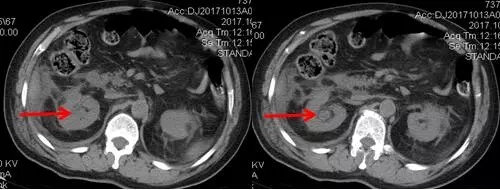

術后CT,箭頭所指為腎結(jié)石被徹底清除

三日后,曾奶奶病情逐漸穩(wěn)定,各項感染指標逐漸恢復正常,復查CT顯示腎結(jié)石已經(jīng)被完全清除,現(xiàn)已康復出院。就此,困擾曾奶奶多年,反復感染差點致命的腎結(jié)石頑疾被徹底治愈。曾奶奶全家人對于愛康醫(yī)院泌尿外科專家高超的碎石取石手術技藝更是贊許有加,對泌尿外科團隊的工作給予衷心感謝和高度評價。